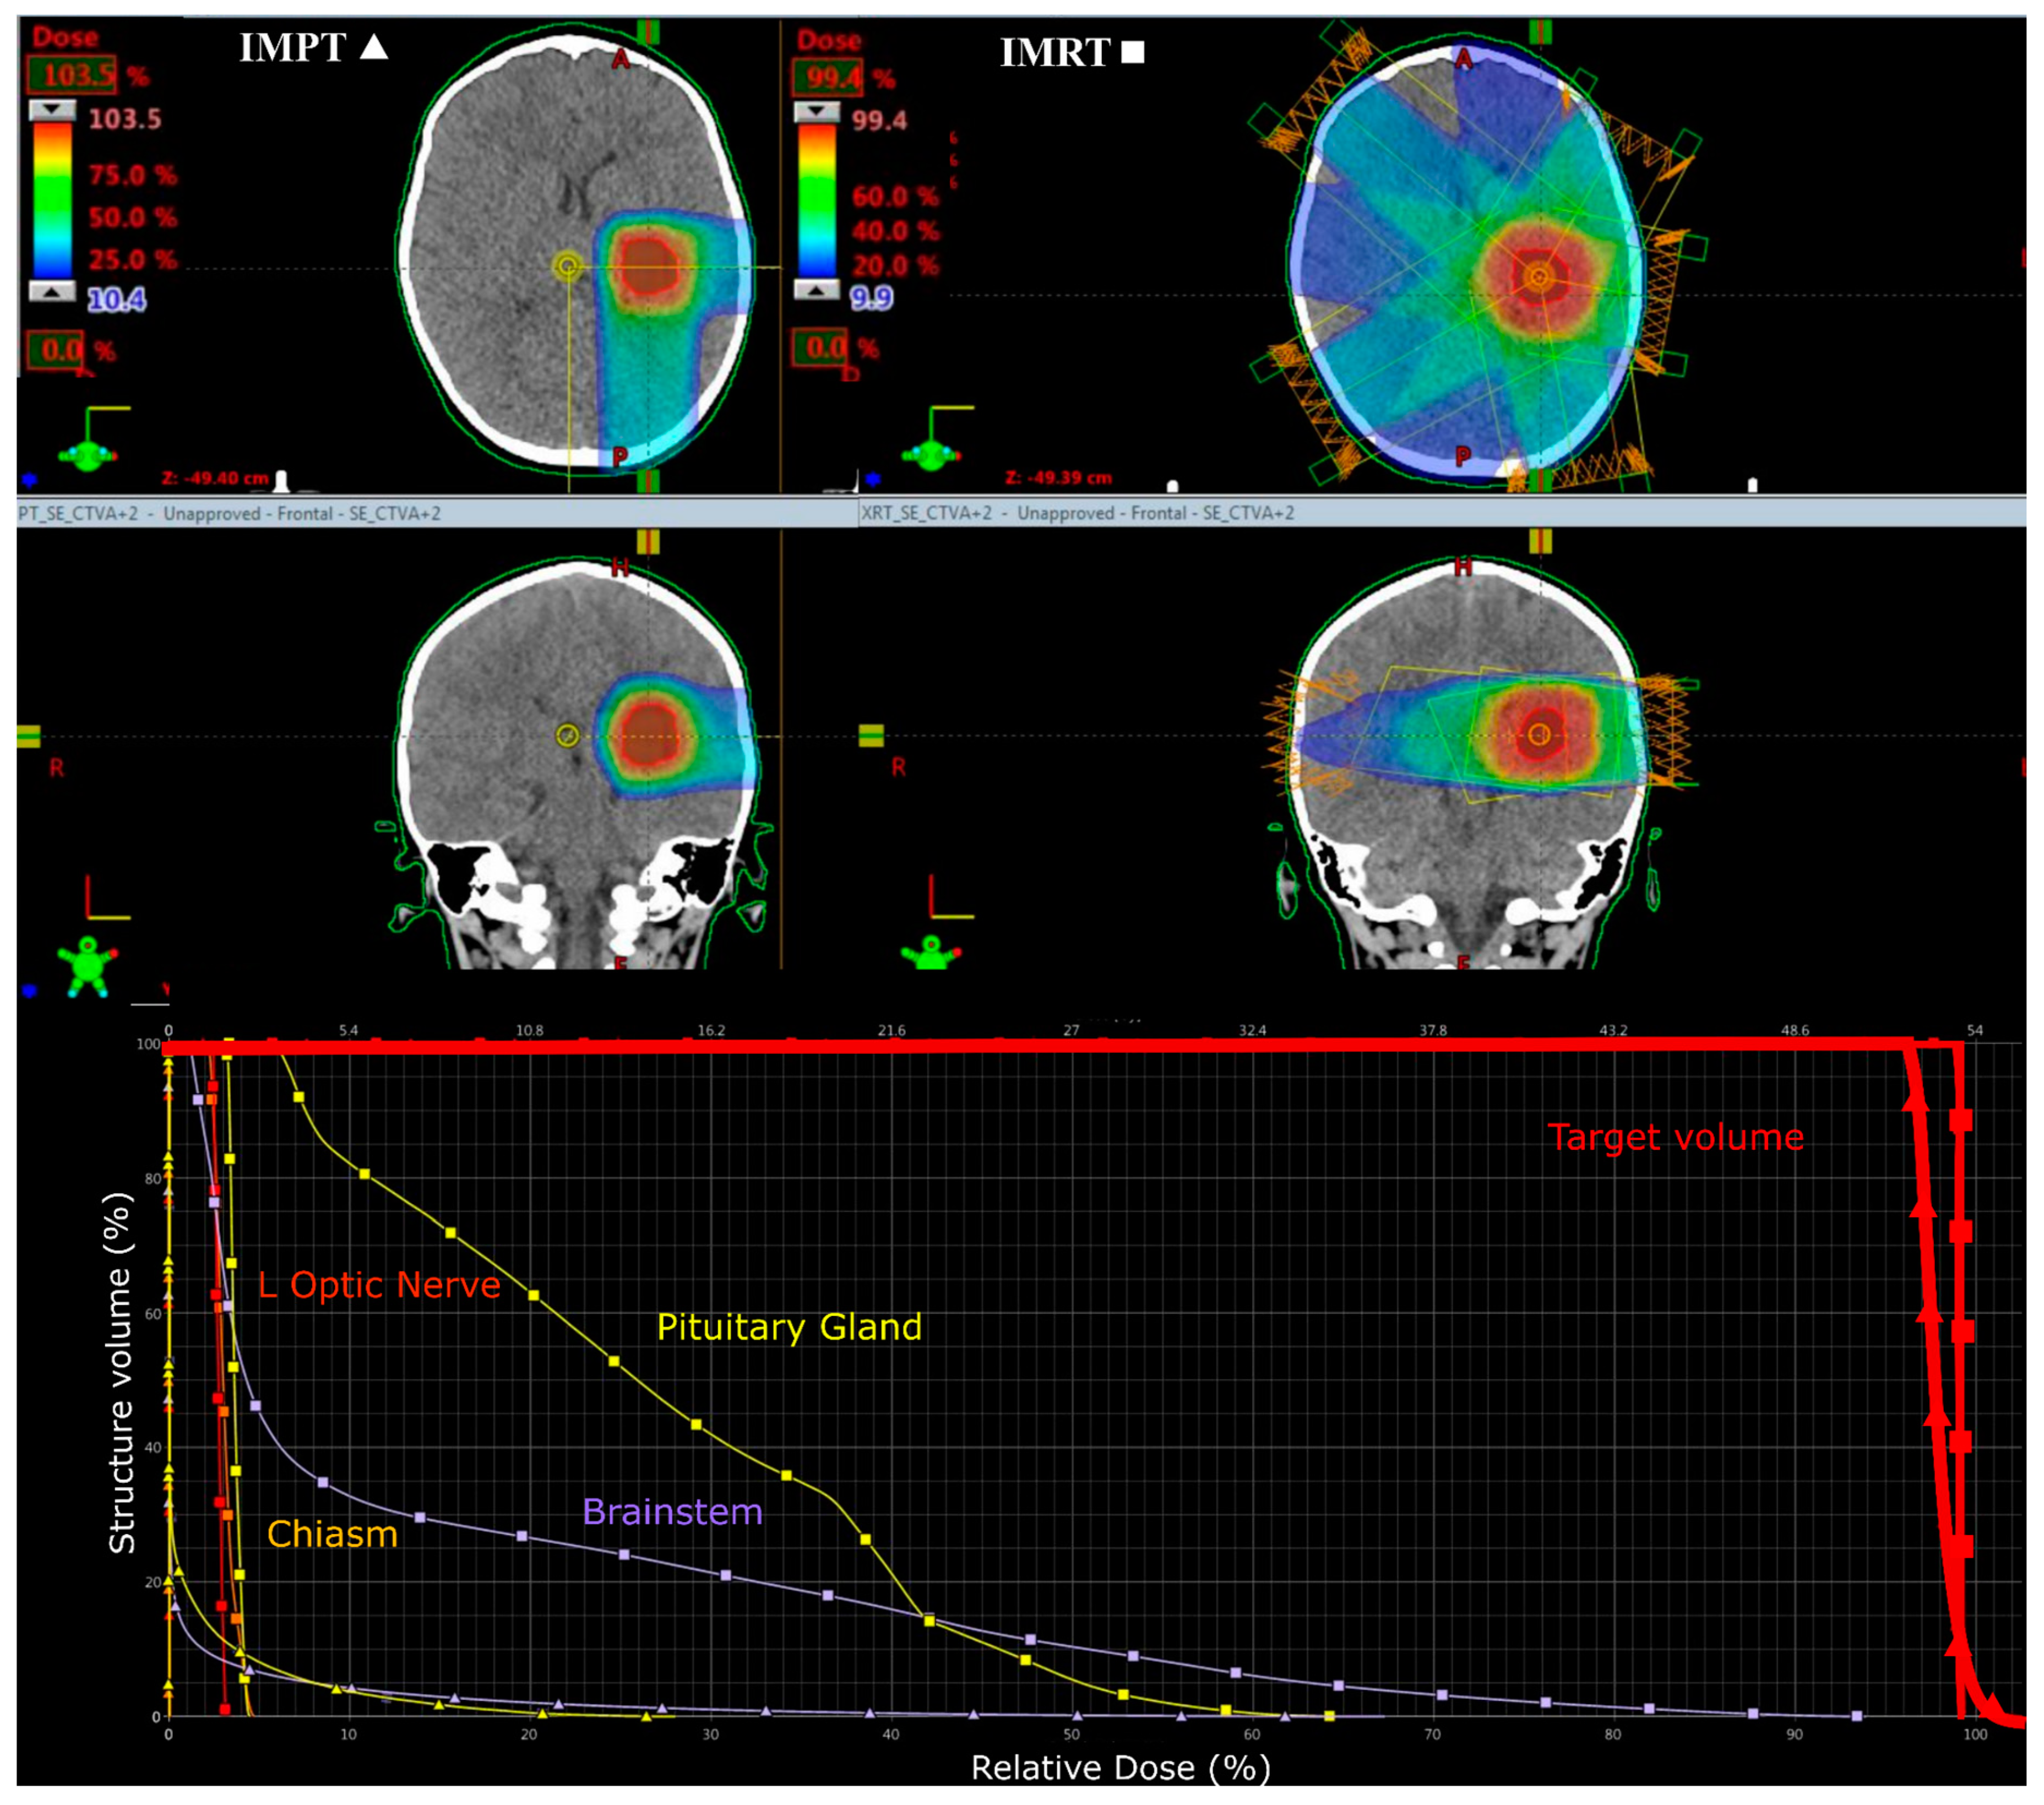

3.2. Supratentorial Ependymoma

2.2.1. Prescribed Dose and Beam Arrangement for Intensity-Modulated Proton Therapy (IMPT)

2.2.2. Prescribed Dose and Beam Arrangement for Intensity-Modulated Photon Therapy (IMRT)